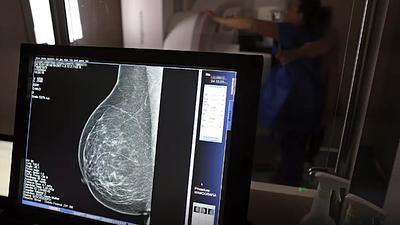

Super Centro usa IA em diagnósticos de câncer de mama

Os laudos dos exames de mamografia realizados no Centro Carioca de Diagnóstico e Tratamento por Imagem (CCDTI) são avaliados e assinados por profissionais médicos capacitados, no entanto, a IA auxilia na identificação de possíveis lesões difíceis de serem vistas.